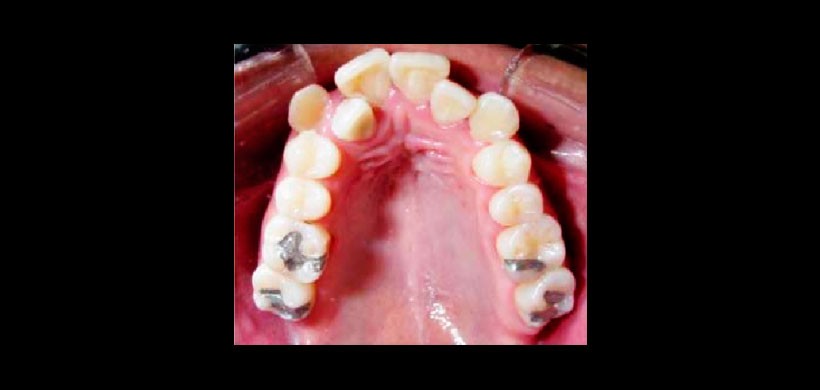

Figura 1: Arco superior, forma de arcada triangular, Incisivos laterales palatinizados, canino izquierdo fuera de arco. Apiñamiento severo.

Figura 5: Cambios transversales.